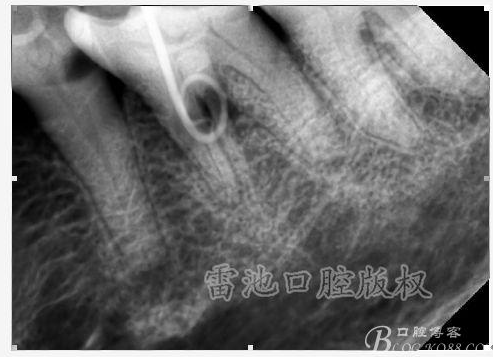

C、牙根的折裂與隱裂 包括橫折,縱折,或者斜折,外傷類的不用討論,主要是某些特殊原因比如牙齒本身結(jié)構(gòu)先天性缺陷再配合后天因素如牙合創(chuàng)傷、咬合平衡發(fā)生改變導(dǎo)致應(yīng)力集中,或者某次瞬間的咬合暴力等一種或者多種因素作用的結(jié)果,具體什么原因這個(gè)要從多方面因素權(quán)衡來(lái)判斷,比如牙齒的松動(dòng)度,詢問(wèn)病史,找不出其它原因時(shí)的重點(diǎn)懷疑,牙齒本事是否處于合應(yīng)力集中的區(qū)域,是否有不良修復(fù)設(shè)計(jì)等等,具體可以通過(guò)臨床“理化檢查(冷熱,叩診等)”再結(jié)合數(shù)值化小牙片,牙髓活力測(cè)定,以及CBCT等來(lái)綜合判斷,重點(diǎn)懷疑牙為上頜的4/5的頰或者腭根,尤其是4或者5的遠(yuǎn)中已是游離缺失或者單端橋等,6的腭根以及下頜的4/5/6都是重點(diǎn)懷疑對(duì)象,而最難診斷的是牙根的隱裂,即使使用CBCT有時(shí)候也沒(méi)辦法確診;